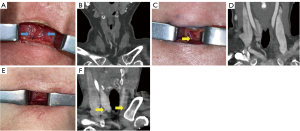

According to our intraoperative data, possible high-platform IAs were found or exposed in 20 (20/127, 15.7%) cases in the older adult group and 7 (7/74, 9.5%) cases in the non-older adult group. Owing to vascular anatomical variations of the IA, we detected prominent vascular pulsations in the cervical tracheotomy field during the physical examination performed as part of the tracheotomy procedure (Videos S1,S2). Thyroid-level tracheotomy (i.e., thyroid anatomy and higher-than-usual tracheal incision) was applied to ensure the safety of these patients. In addition, we compared the intraoperative exposure of the pre-tracheal vessels in the older adult patient group, which corroborated the image findings of the CECT/CTV analysis (Table 4 and Figure 2). The types of AJV, IA, and ITVP communicating branch were related to the location of the tracheal incision in the older adult group (rn=0.28, rn=0.59, and rn=0.267, all P<0.01; Table 4 and Tables S3,S4). All the single-branch and multi-branch AJVs in both groups were exposed in the second to fourth tracheal cartilage region, namely the so-called the OSTs’ common zone.

The incidences of all the post-OST complications were not statistically different (P=0.441) between the two groups. After the OST procedure, 7 patients (5.5%) in the older adult group and 3 patients (4.1%) in the non-older adult group were reported for minor bleeding after OST, which had been resolved by conservative measures. Three patients (2.4%) in the older adult group and 1 patient (1.4%) in the non-older adult group encountered active bleeding complications requiring reoperations for hemostasis. According to the reoperation medical records, the main unattended vessels/structures (causes for active bleeding) were AJVs (1 in the older adult group and 1 in the non-older adult group), ITVP (1 in the older adult group) and thyroid isthmus (1 in the older adult group). Though the rate of bleeding-related complications, on the whole, were not statistically different between the two groups (P=0.901), there is still an increasing likelihood of post-OST bleeding in the older adult group (10/127, 7.9%) when compared with that in the non-older adult counterpart (4/74, 5.4%). Given that most tracheotomies in this study were elective rather than emergency/impromptu, no recurrent laryngeal nerve injury or tracheoesophageal fistula occurred in this study. However, severe post-OST subcutaneous emphysema and pneumothorax were only reported in 2 and 1 patients in the older adult group, respectively (Video S3 and Figures S2,S3). We used scatter plots to visualize the numerical distribution of variables and quantify the correlation, with coefficients of determination r2 values of 0.190, 0.459, and 0.451 respectively. The distance from the upper edge of IA to the upper edge of the sternal stem notch was moderately correlated with the commonly used incision position (r=0.436). The correlation coefficient of the older adult group (r=0.313) was smaller than that of the non-older adult group (r=0.651). The distance from the midpoint of the second to fourth tracheal ring to the lower edge of thyroid isthmus and the distance from the lower edge of thyroid isthmus to the upper edge of the sternal stem notch were interpreted as having a strong correlation with the commonly used incision position (r=0.677 and r=0.672, respectively); the correlation coefficient of the older adult group (r=0.665 and r=0.668, respectively) was greater than that of the non-older adult group (r=0.560 and r=0.661, respectively) (Figure 3).

The IA is one of the three major branches of the aorta, and its location around the trachea depends primarily on its morphology, neck length, and inspiratory/expiratory status. We found that the proportion of platform-type IAs in the older adult group (37%) was much higher than that in the non-older adult group (13.6%). This finding validates the claim that the IA and carotid twisting and kinking become more pronounced as age increases (11). Therefore, during emergent OSTs for older adult patients, caution should be paid to the possibility of high-platform IA variants. In some rare cases, the IA may reach or even exceed the level of the thyroid isthmus (extreme high-platform type), largely interfering with routine OST incisions. From our perspective, the high position of IA, with its partial segment extending above the second to fourth tracheal ring, may also involve a considerable risk of fatal iatrogenic bleeding during OST procedures (11,12,26-32). Accidental life-threating injury of the IA has even been attributed to the existence of such uncommon variants (11,26-30,32). For older adult patients with strong pre-tracheal vessel palpation signs, CECT or CTA could be possibly arranged for analysis of IA and OST-related issues. In addition, under these IA circumstances, nasal intubation or higher elective or emergent tracheal incision should be attempted to avoid severe OST complications.